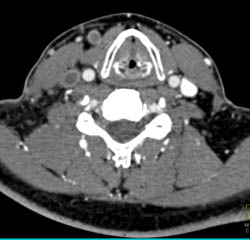

Jugular Vein Thrombosis